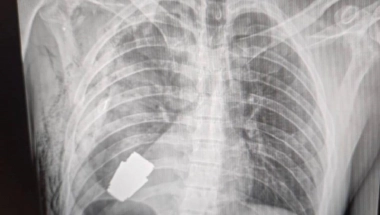

Na rendgenskom snimku vidi se granata, a na drugoj hirurg s komadom metala u krvavim rukavicama.